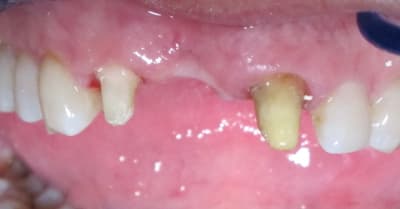

j'aurais bien aimé voir le défaut osseux/gingival dessous...

parce que quitte à faire le bridge, un bon steak de conjonctif enfouis pour redonner du volume au niveau de la dent absente, un bridge prov pendant la phase de cicat avec un ovate pontique et amha plus besoin de cette fausse gencive...

Pour ce cas: pas de temps et pas d'argent, donc solution de compromis.

J'essaye de poster des photos sans la pap.